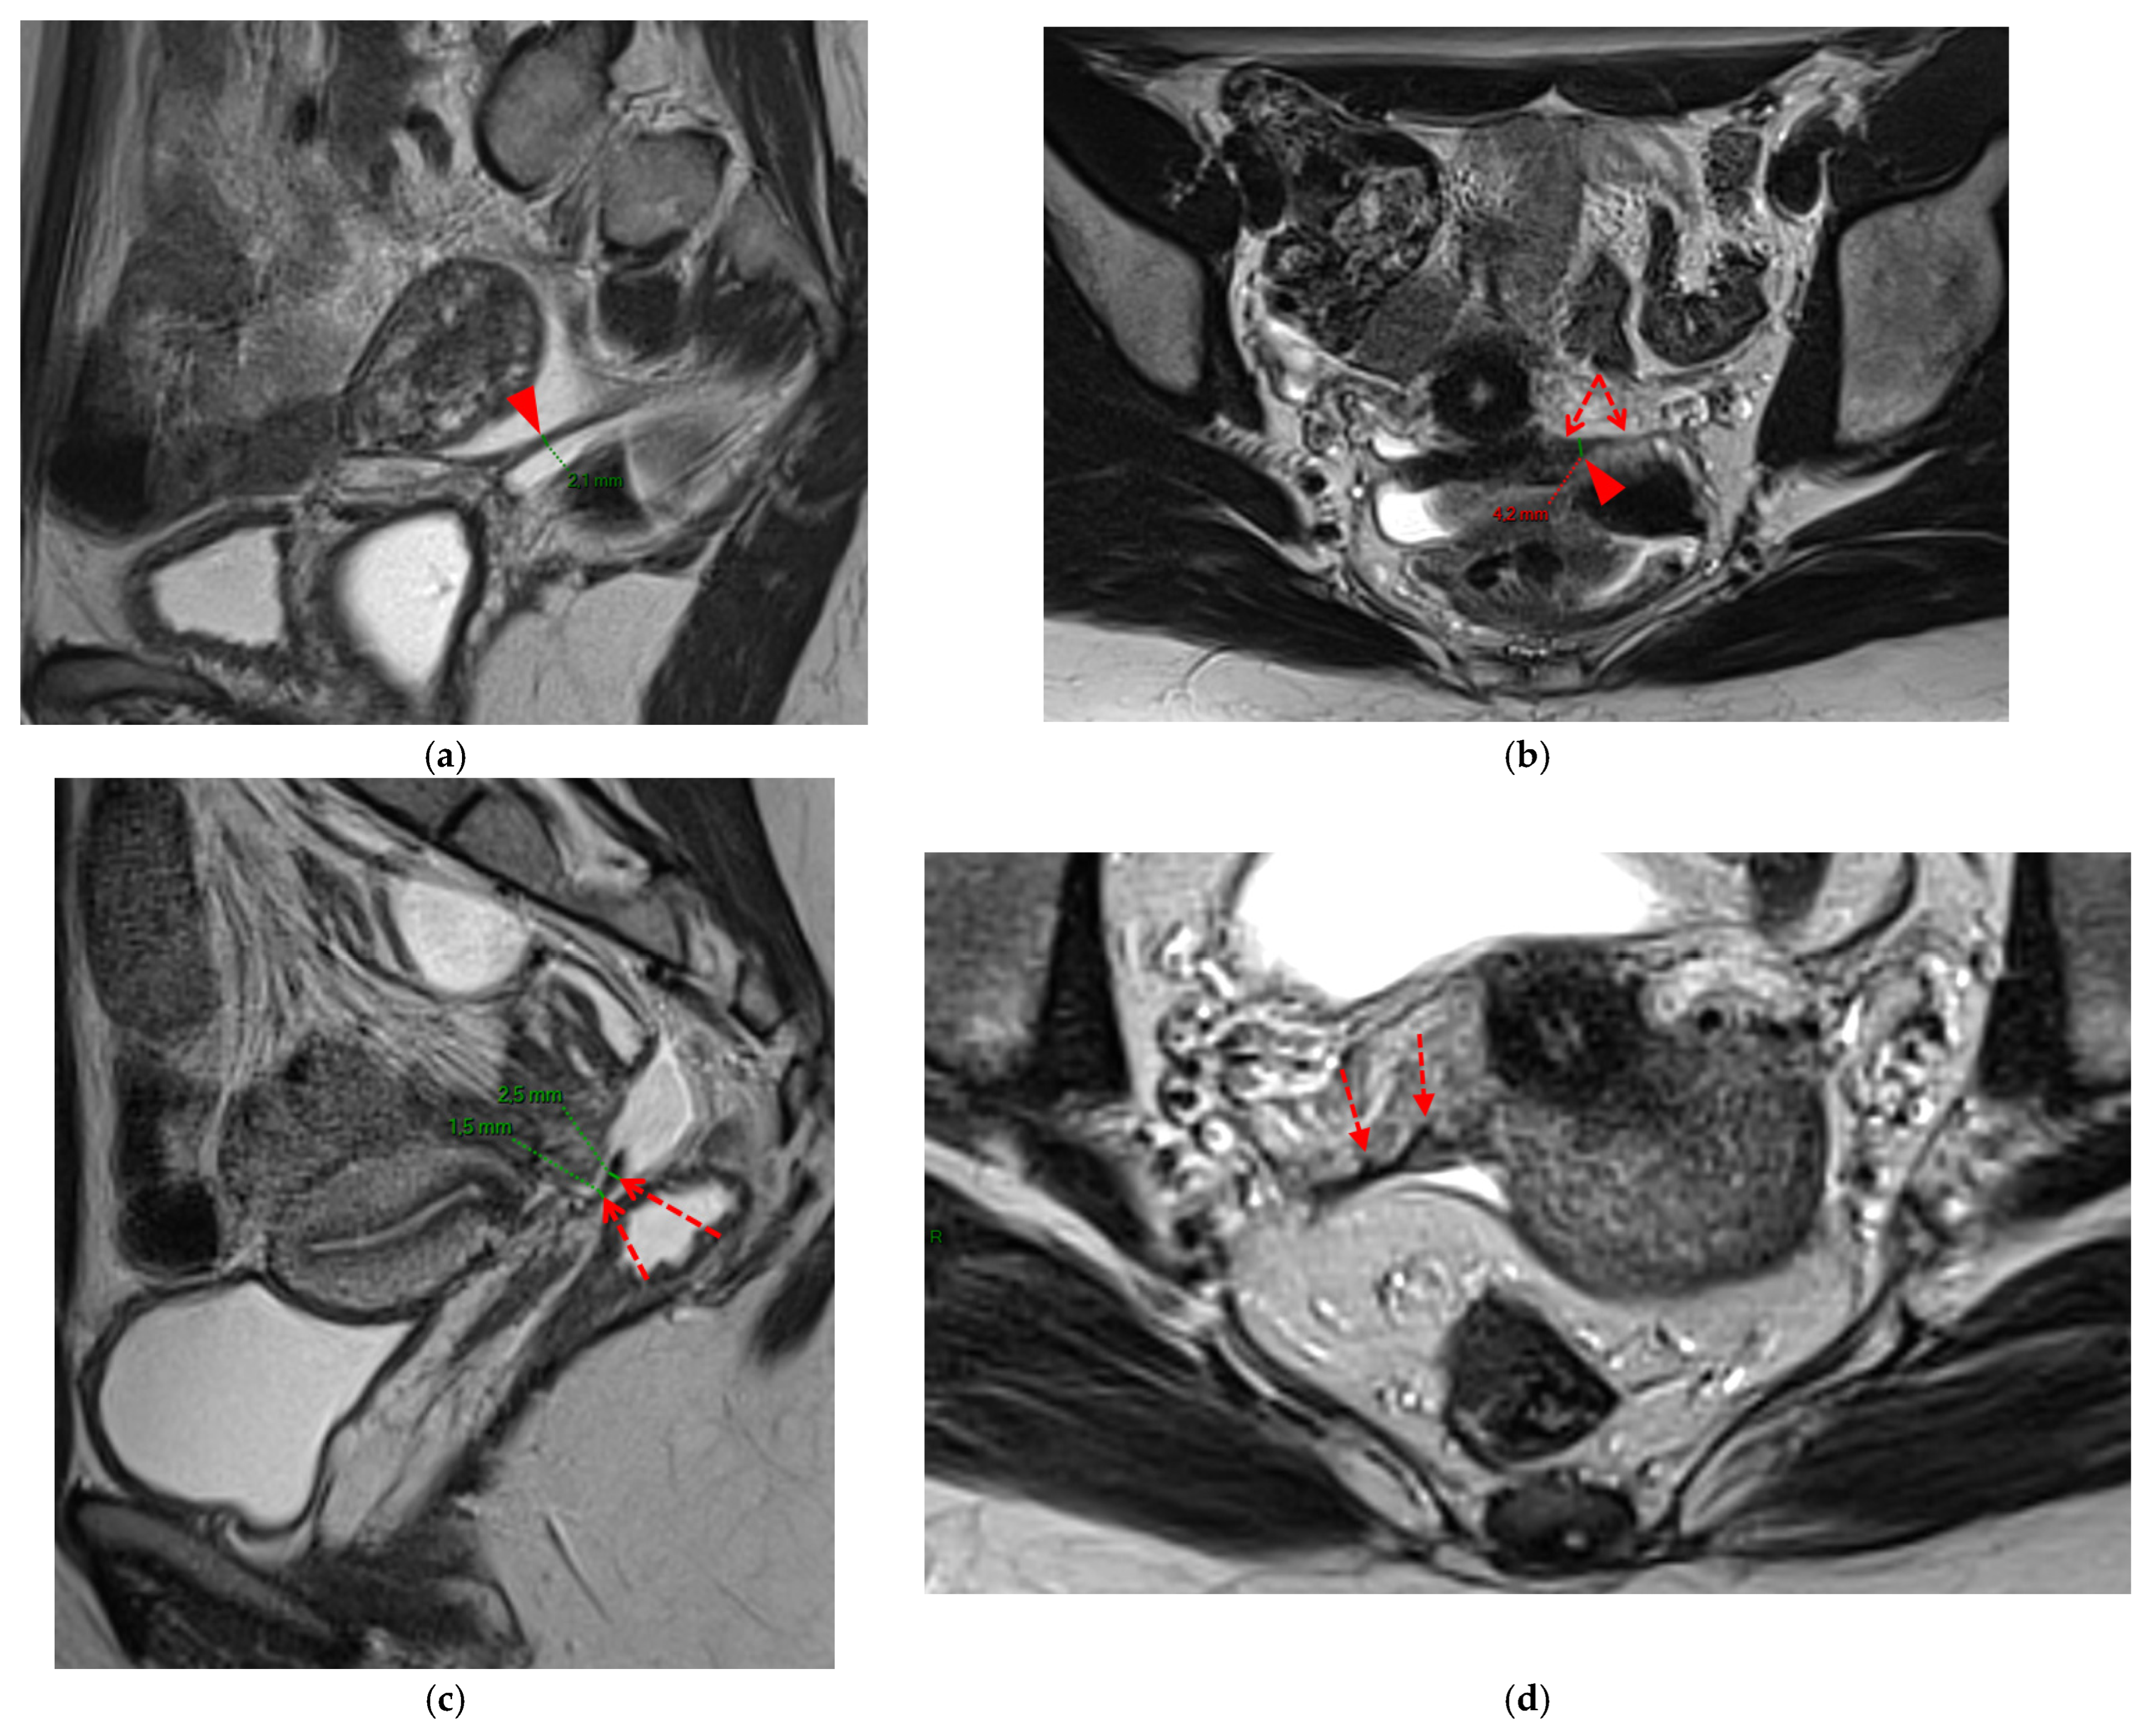

A type 3B USL (Figure 4), in addition to being thickened, has a notched surface with slightly irregular margins, or a caliber disparity with focal thickening, or appears “stiffened”, which means it loses its curvilinearity to exhibit a steep vertical orientation in the sagittal plane or a “bowstringing” of the USL in the sagittal or axial planes. Occasionally, a USL might appear thin but “stiffened”, which would upgrade it from a type 2 to a type 3B.

Figure 4. Pelvic MRI scans of seven patients with HTD type 3B USLs. (a) Sagittal T2WI: a thickened (2.1 mm) and stiffened right USL (arrowhead) with “bowstringing”. (b) Axial T2WI: a caliber disparity (dashed arrows) with focal thickening (4.2 mm) of the left proximal USL (arrowhead). (c) Sagittal T2WI: a caliber disparity (dashed arrows) with focal thickening (2.5 mm) of the right distal USL. (d) Axial T2WI: a right USL with a notched and irregular surface (dashed arrows). (e) Axial T2WI: thickened and stiffened left (3 mm) and right (2.5 mm) USLs with “bowstringing” of both USLs (arrowheads). (f) Sagittal T2WI: a thickened (2.6 mm) right USL with a stiffened appearance characterized by a steep vertical orientation (arrowhead). (g) Sagittal T2WI: the right USL appears thin (1.9 mm) but stiffened (arrowhead), exhibiting “bowstringing”. These findings led to its reclassification from type 2 to type 3B.